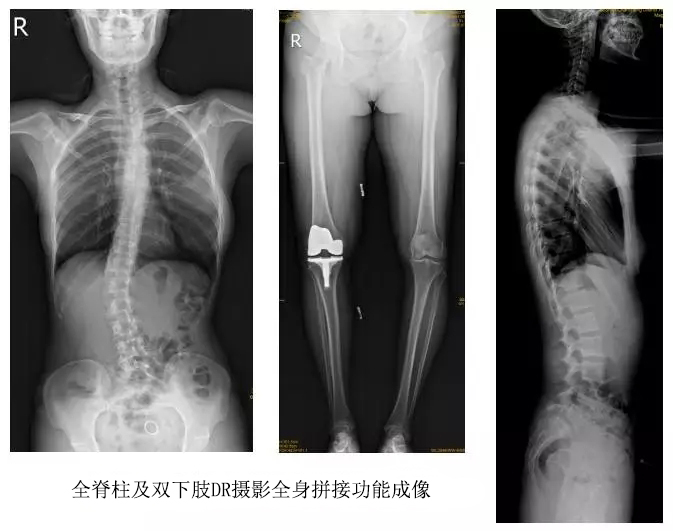

技術(shù)日新月異,隨著DR全身拼接功能的可實(shí)現(xiàn),有效解決了全脊柱及全下肢的完整成像。

以某院所攝X光片為例,對(duì)比傳統(tǒng)攝片與全身拼接功能的區(qū)別:

傳統(tǒng)X光片只能觀察每個(gè)部位的局部情況,無法在統(tǒng)一體上進(jìn)行連續(xù)、全面的觀察,全脊柱及下肢全長片則能直觀的看到整體形變。通過DR全身拼接功能實(shí)現(xiàn)的完整成像,為診治脊柱及下肢畸形提供了完美的臨床影像依據(jù),對(duì)臨床診斷、術(shù)前手術(shù)方案的制定和術(shù)后療效的評(píng)估等臨床應(yīng)用具有十分重要的意義,有效滿足了此類疾病臨床診斷和治療的要求。